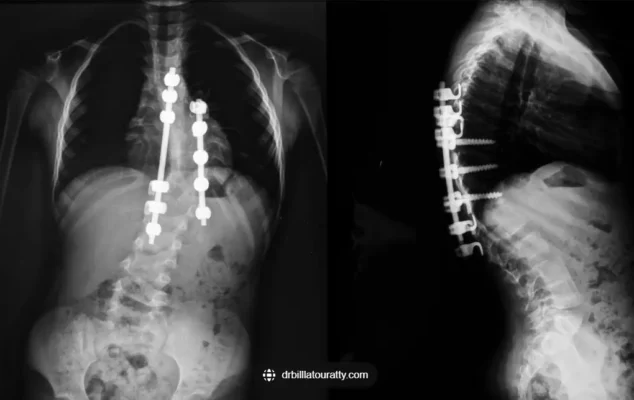

Recuperación de la cirugía de escoliosis: Qué esperar durante el periodo de recuperación tras una cirugía de escoliosis

Tras una operación de escoliosis, el periodo de recuperación es crucial para que los pacientes recuperen la fuerza y la movilidad. [...]

Tiempo de recuperación de la cirugía de escoliosis: Comprender los plazos de recuperación y los cuidados postoperatorios tras la cirugía de escoliosis

El tiempo de recuperación de la cirugía de escoliosis varía en función de la persona y de la complejidad de la intervención. [...]